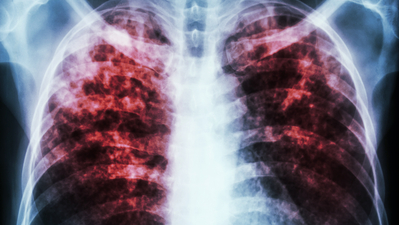

In most people infected by tuberculosis, tuberculosis bacteria attack the immune cells of the lungs. The immune cells fight the bacteria by eating them. But the tuberculosis bacterium has developed various evasive mechanisms that reduce the immune cells’ ability to digest and thus to kill the Mtb.